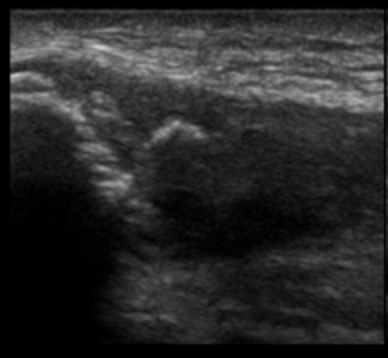

Knee Patellar Tendinosis Long Axis Image